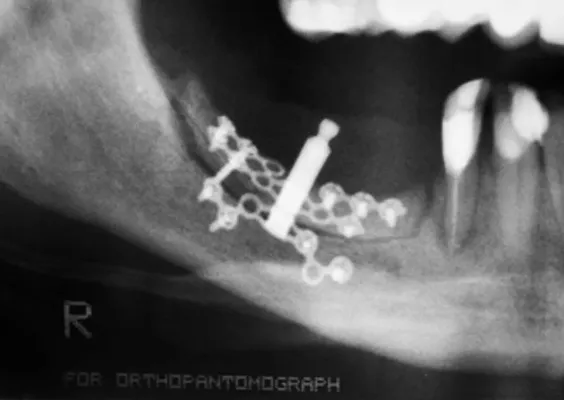

ZASTOSOWANIE DYSTRAKTORÓW KOSTNYCH ORAZ TECHNIK OSTEOGENEZY DYSTRAKCYJNEJ W ZAKRESIE WYROSTKA ZĘBODOŁOWEGO SZCZĘK I ŻUCHWY

Obecnie rzadko stosowana metoda odbudowy tkanki kostnej, która bazuje na naukowych podstawach z lat pięćdziesiątych ubiegłego stulecia. Prof. Ilizarov jako pierwszy opisał tę technikę, polegającą wówczas na wydłużaniu kości długich ludzkiego szkieletu. Metodę tę adaptowano dla potrzeb korekcji wad wrodzonych twarzowo-szczękowych oraz rekonstrukcji ubytków i deformacji kostnych w zakresie wyrostka zębodołowego szczęk i żuchwy.

Do wydłużenia i poprawy kształtu kości poddanej korekcie techniką osteogenezy dystrakcyjnej wykorzystuje się specjalne aparaty nazywane dystraktorami. Działają one poprzez rozkręcanie śrub, które aktywują proces wydłużania kości. W zależności od budowy dystraktora mogą one działać jedno-, dwu- lub trójwektorowo, czyli tylko wydłużać kość, rozciągać ją płaszczyznowo lub przestrzennie.

Aby zestaw rozciągający zadziałał, należy aktywować samą kość. Do aktywacji dochodzi na skutek nacięcia zewnętrznej, twardej blaszki kostnej, tzw. korowej, na zadanym kierunku lub pełnoprzekrojowego przecięcia kości. Po okresie kilku dni, gdy zaczyna się wytwarzać tkanka kostna bliznowata w miejscu przecięcia, rozpoczyna się aktywne rozkręcanie aparatu, a przez to wydłużanie wraz z wtórnym modelowaniem tkanki bliznowatej, która następnie mineralizuje się w strukturę kostną.

Istnieje wiele koncepcji ostedystrakcji, ich autorzy stworzyli własnego pomysłu opatentowane konstrukcje dystraktorów. Niektóre mają nieskomplikowany system działania, natomiast służą do powolnej i fizjologicznej korekty nawet bardzo dużych wad czaszkowo-szczękowo-twarzowych oraz ortognatycznych.